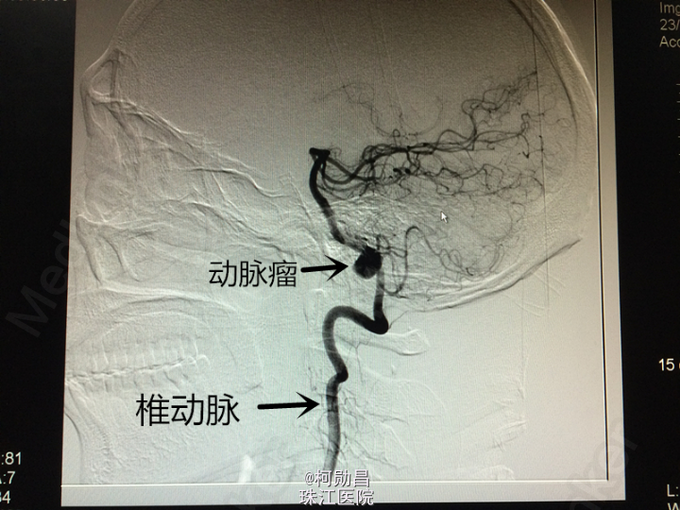

脑血管病入门级(3)-------LVA动脉瘤1例

患者49岁男性,因“头痛1个月,加重1周”入院,曾于2007年无明显诱因突发头痛、意识不清,行头颅CT检查示:蛛网膜下腔出血。于保守治疗后病情好转,未作进一步DSA检查等。入院前1个月患者再次出现头痛,左侧为主,呈爆炸样痛,无呕吐、意识障碍等。行头颅CTA检查提示:“左侧椎动脉动脉瘤”